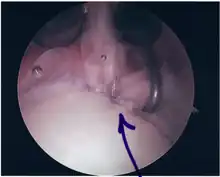

Surgical treatment of SLAP tears has become more common in recent years. The success rate for repairing isolated SLAP tears is reported between 74-94%.[7] While surgery can be performed as a traditional open procedure, an arthroscopic technique[8] is currently favored being less intrusive with low chance of iatrogenic infection.[9]

Procedure

Following inspection and determination of the extent of injury, the basic labrum repair is as follows.

- The glenoid and labrum are roughened to increase contact surface area and promote re-growth.

- Locations for the bone anchors are selected based on number and severity of tear. A severe tear involving both SLAP and Bankart lesions may require seven anchors. Simple tears may only require one.

- The glenoid is drilled for the anchor implantation.

- Anchors are inserted in the glenoid.

- The suture component of the implant is tied through the labrum and knotted such that the labrum is in tight contact with the glenoid surface.